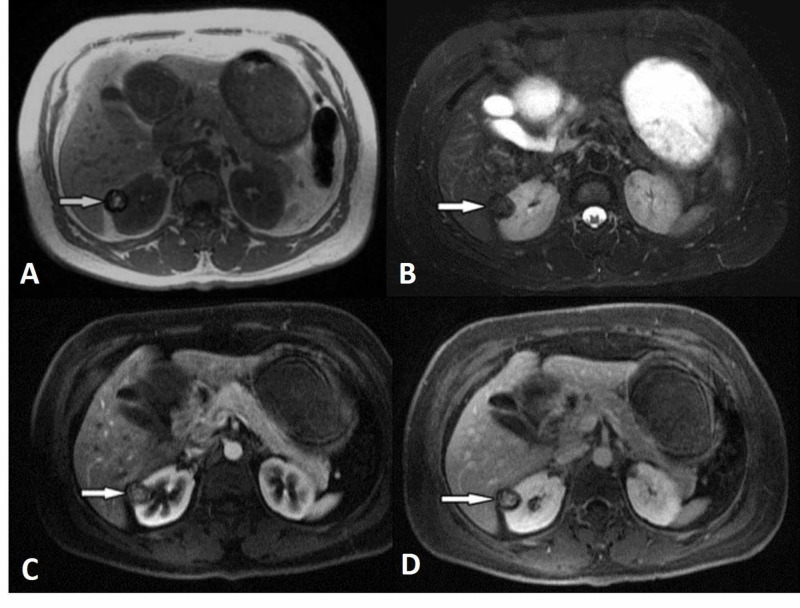

Figure 2. Papillary RCC example from the same review. The lesion is well-demarcated, hypovascular, and T2-dark, which is why papillary RCC can feel much less dramatic than clear cell RCC and sometimes drift toward cyst or fat-poor AML confusion. Source:

Morshid et al., Figure 4

, Creative Commons Attribution License.2

| Papillary-leaning pattern25 | Homogeneous low-level enhancement, T2 hypointensity, precontrast hyperattenuation, or a pseudocystic look | Papillary RCC can look less dramatic than clear cell RCC and is easier to confuse with hemorrhagic cyst or fat-poor AML |

Clear cell RCC is the classic hypervascular subtype. It often enhances similarly to cortex in the corticomedullary phase, can look heterogeneous, and is more likely to show necrosis or venous invasion in aggressive cases.2 Papillary RCC usually sits at the opposite end of the spectrum: more hypovascular, often more homogeneous when small, frequently T2-dark, and sometimes hyperattenuating before contrast, which is why it can drift toward cyst or AML confusion.25 Chromophobe RCC often falls in between, with more intermediate enhancement and enough overlap with oncocytoma that imaging may stay suggestive rather than pathology-level definitive.24